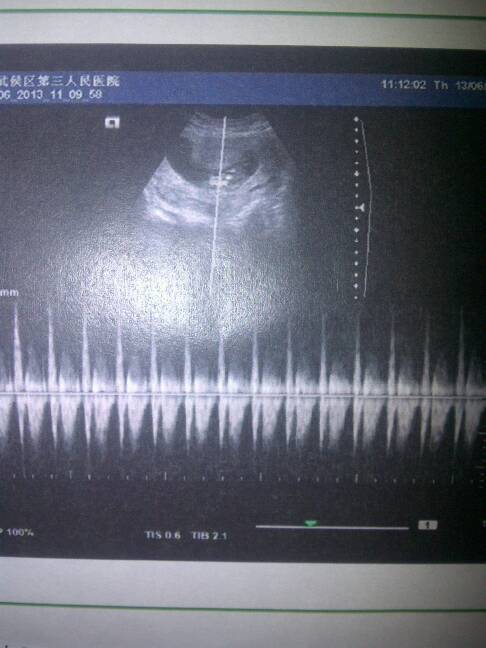

请大家帮我看看怀孕两个半月的bc单,孩子能看出是男是女吗?

??? 这个 ...有一点点的预兆 照这个图片来看 有六成半可能是个女孩 ....你不会看着是女孩就准备打掉吧?????